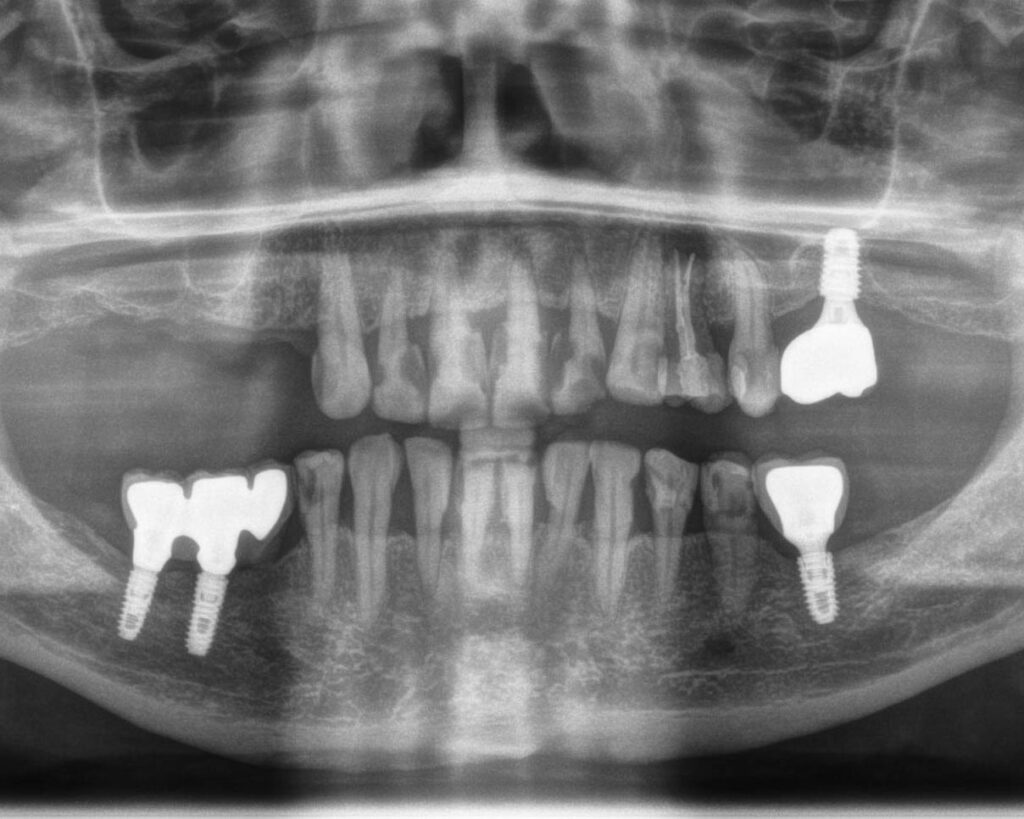

An implant is an artificial tooth root that replaces a lost tooth. It is made of titanium—a material well tolerated by the body—which fuses with the bone. This creates a strong foundation for the crown, the visible part of the tooth that looks and functions like a natural tooth.

Implants are perfect for replacing single missing teeth, and for larger gaps, several implants can support a fixed restoration for an entire jaw or lower jaw. Many patients worry about pain, but it’s important to remember that implant placement is done under anesthesia, and post-procedure discomfort is comparable to that after a regular tooth extraction.

Thanks to titanium, implants are biocompatible, meaning they integrate perfectly with the patient’s bone and even promote bone regeneration. High-quality implants, such as those from Osstem, often come with a lifetime warranty (of course, excluding the bone!), which confirms their reliability.